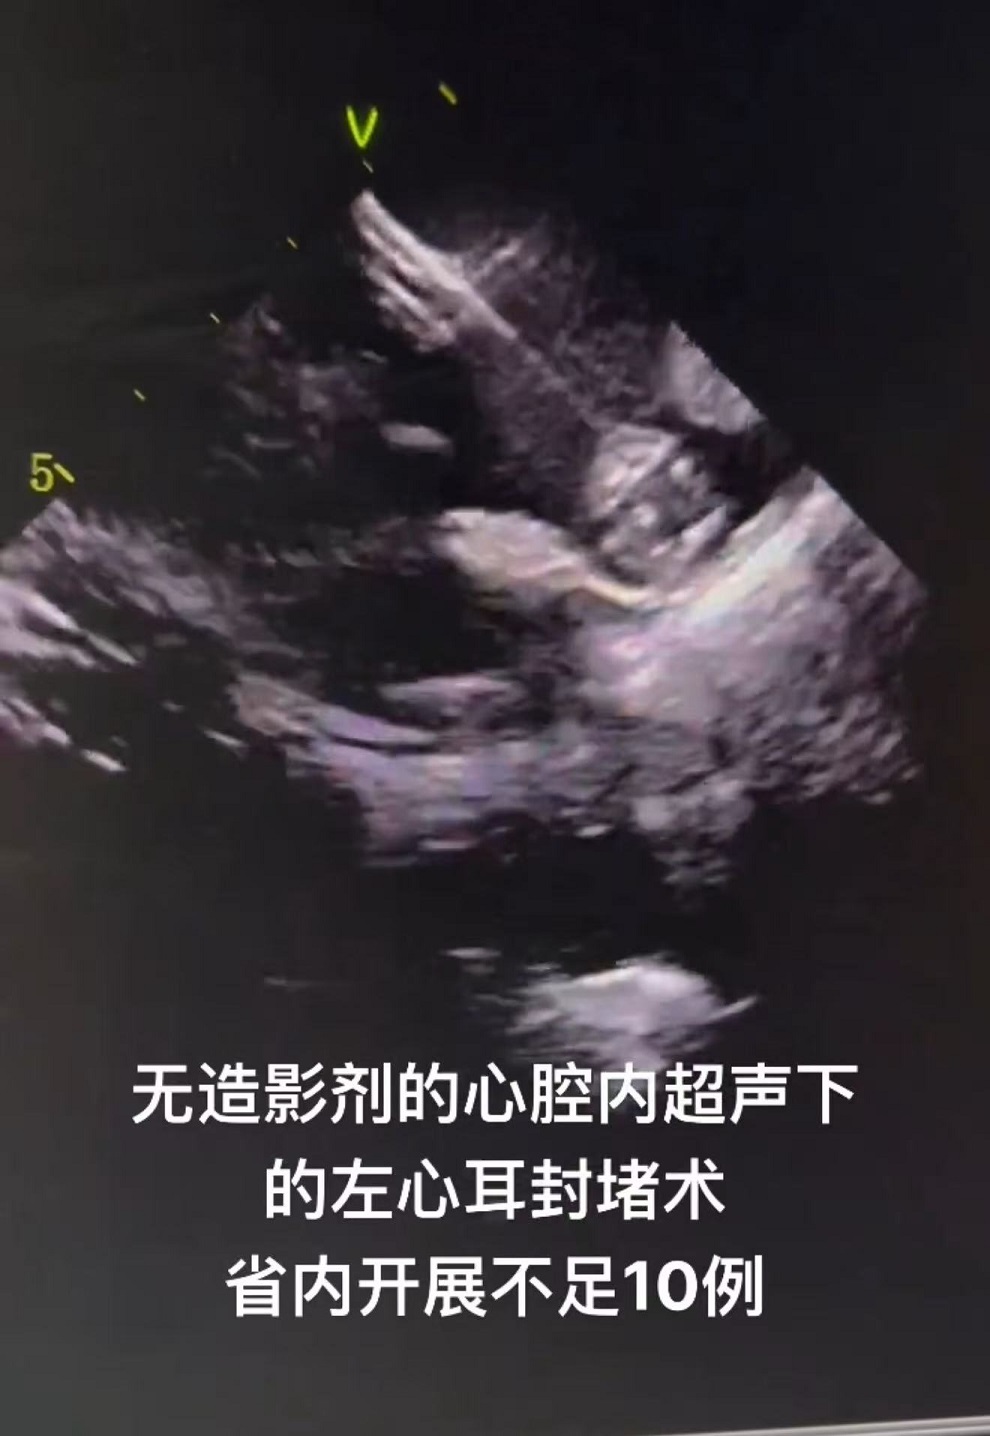

1. 病人72岁男患者,既往冠脉造影术中发生严重造影剂过敏导致休克,患者持续房颤20年病史,CHA2DS-VASC评分4分,HAS-BLED评分4分,左心耳封堵适应症强。常规左心耳封堵术需要再X线下做左心耳造影后,选择合适的封堵伞封堵。该病人术中无法使用造影剂。张晓君主任术前制定了周密手术方案,术前与我院心脏超声科经食道超声精确测量了左心耳各径线直径,术中张主任穿刺房间隔后在心腔内超声的引导下,选取27mm直径的左心耳封堵器成功封堵左心耳。术后患者恢复良好。该类零造影剂下的左心耳封堵术山东省为第四例,国内领先。